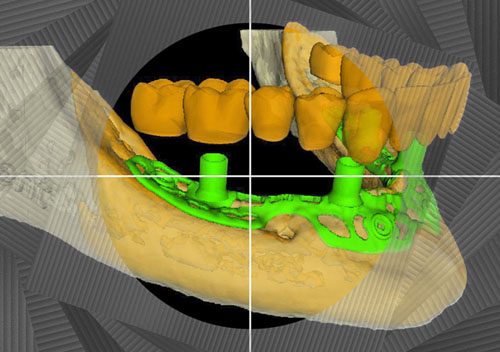

2. После этого произвели компьютерное моделирование самого имплантата и фиксирующих элементов. Примечательно, что в абатментах, использовался отлично зарекомендовавший себя и проверенный десятилетиями интерфейс КОНМЕТ! В результате получили несколько специальных файлов, позволяющих не только сделать сам имлантат, но еще до операции изготовить и сами зубы. Данные файлы передали в изготовление на специальном 3D оборудовании.

Посмотрите на небольшом клиническом примере новый подход к конструированию имплантата по сравнению с имплантатами описанными в начале этой статьи.

Для просмотра проведите курсором мыши по изображению имплантата